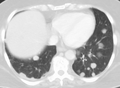

CT image of a lung metastasis

Metastatic cancer in the lungs